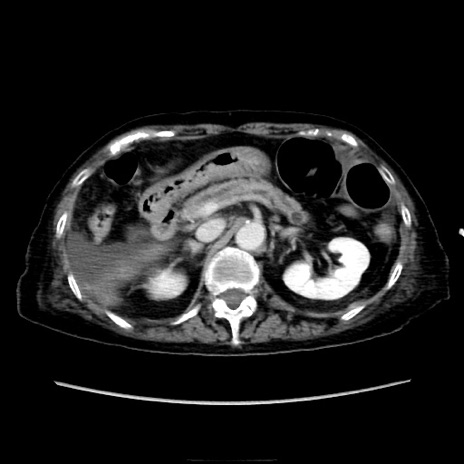

症例40(横断像)

横断像